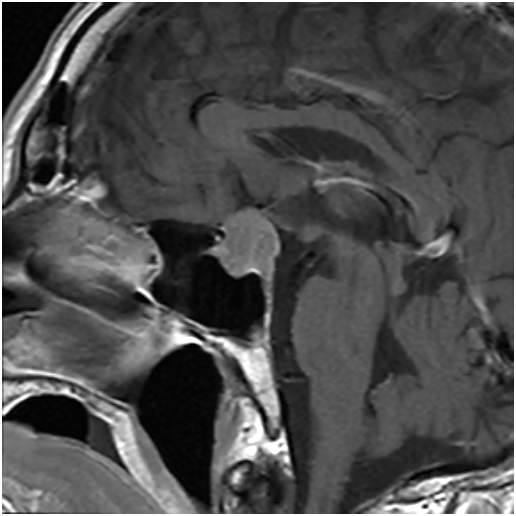

术中的情况。可见肿瘤藏在各个条索状分隔里,分离分隔。吸除肿瘤,尽量清除条索样物。可见鞍膈下降。术后患者诉视力明显改善。眼睛暴胀感消失。

术后显示肿瘤切除满意,正常垂体及垂体后叶后叶保留,术后患者诉视力明显改善。眼睛暴胀感消失。视力基本正常范围。